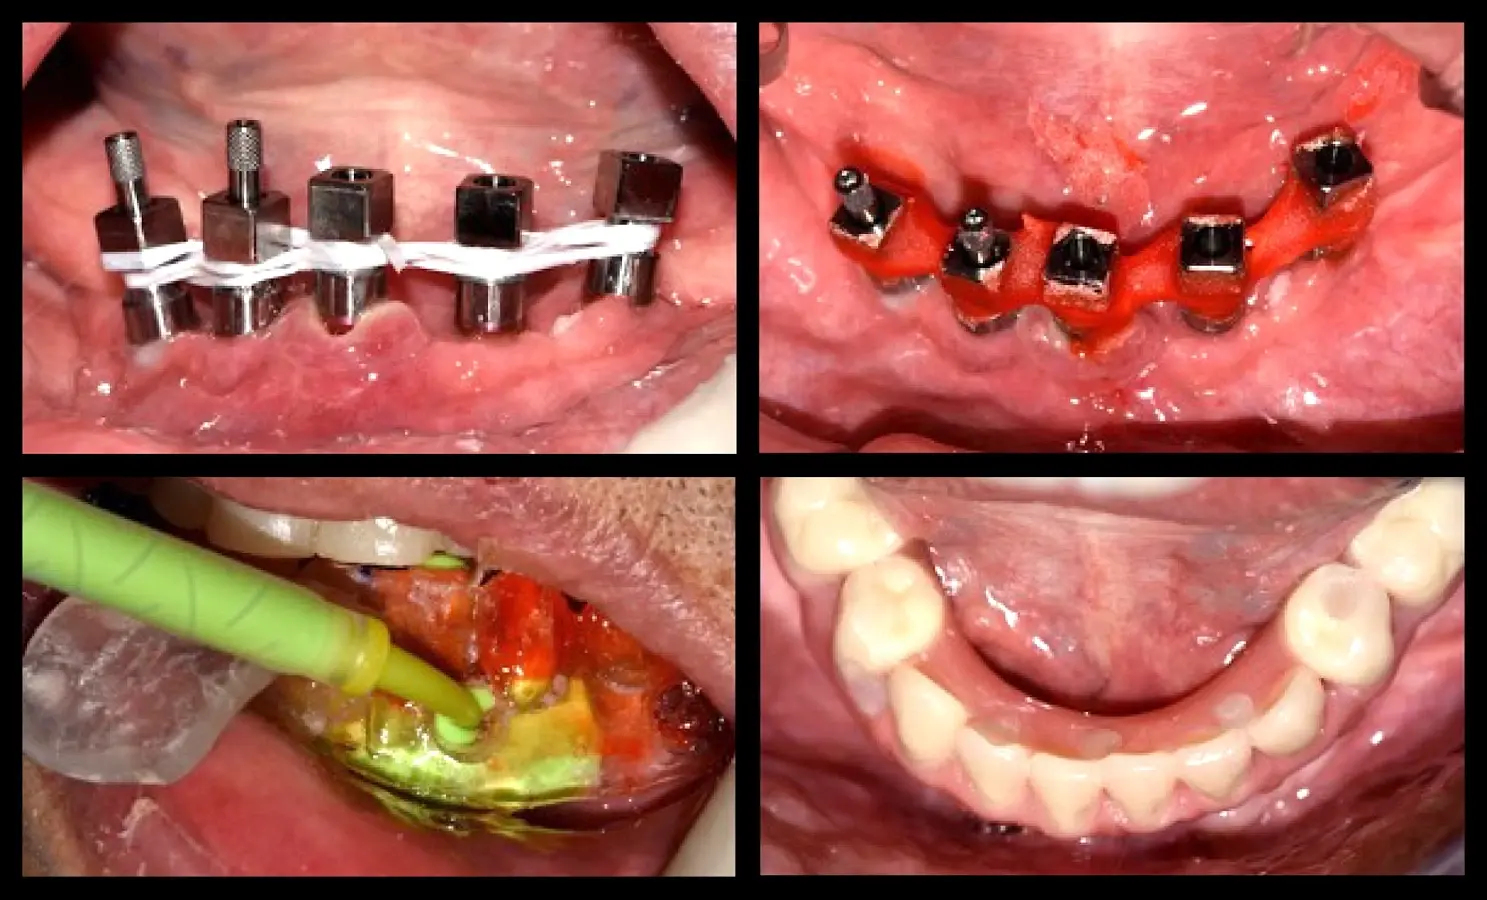

La segunda fase quirúrgica y colocación de pilares intermedios fue realizada en la semana 18, siguiendo la recomendación del fabricante con un torque de 20 Ncm. Se realizó la impresión del maxilar superior y la transferencia de los implantes del maxilar inferior. Una vez corroborado el asentamiento de ambas estructuras en boca se envió al laboratorio para el enfilado de la estructura inferior. Finalizada la prótesis fue instalada en el paciente (Figura 10).

Rehabilitación fina

Figura 10. Rehabilitación final: toma de impresión mediante la técnica de la guía multifuncional.

Se realizó la preparación del lecho periimplantar según el protocolo del fabricante (Unitite, S.I.N.). La secuencia de preparación de los implantes implicó la primera preparación del implante en posición C, en concordancia con la línea media del paciente, y que nos sirvió de guía para la preparación de los demás lechos quirúrgicos. Los siguientes lechos quirúrgicos preparados fueron los distales (Posición A y E); dicha preparación fue orientada hacia distal para mejorar la distancia antero-posterior y reducir así el efecto de palanca distal; finalizando con los de posición B y D. Se colocó la guía quirúrgica para revisar la emergencia en relación a la superficie oclusal de los dientes. La secuencia de fresado del fabricante (UNITITE, S.I.N.) es fresado intermedio, en donde el diámetro de la fresa final es 0.20 mm menor al diámetro del implante. El fresado intermedio reduce la cantidad de microfisuras a nivel de las roscas del implante, y favorece la neoformación ósea a nivel de las cámaras de cicatrización. Procedimos con la colocación de los implantes de 3.5 mm de diámetro y 10 mm de longitud (UNITITE, S.I.N.) (Figura 6).

Colocación de implantes dentales

Figura 6. Colocación de implantes dentales con superficie activada.